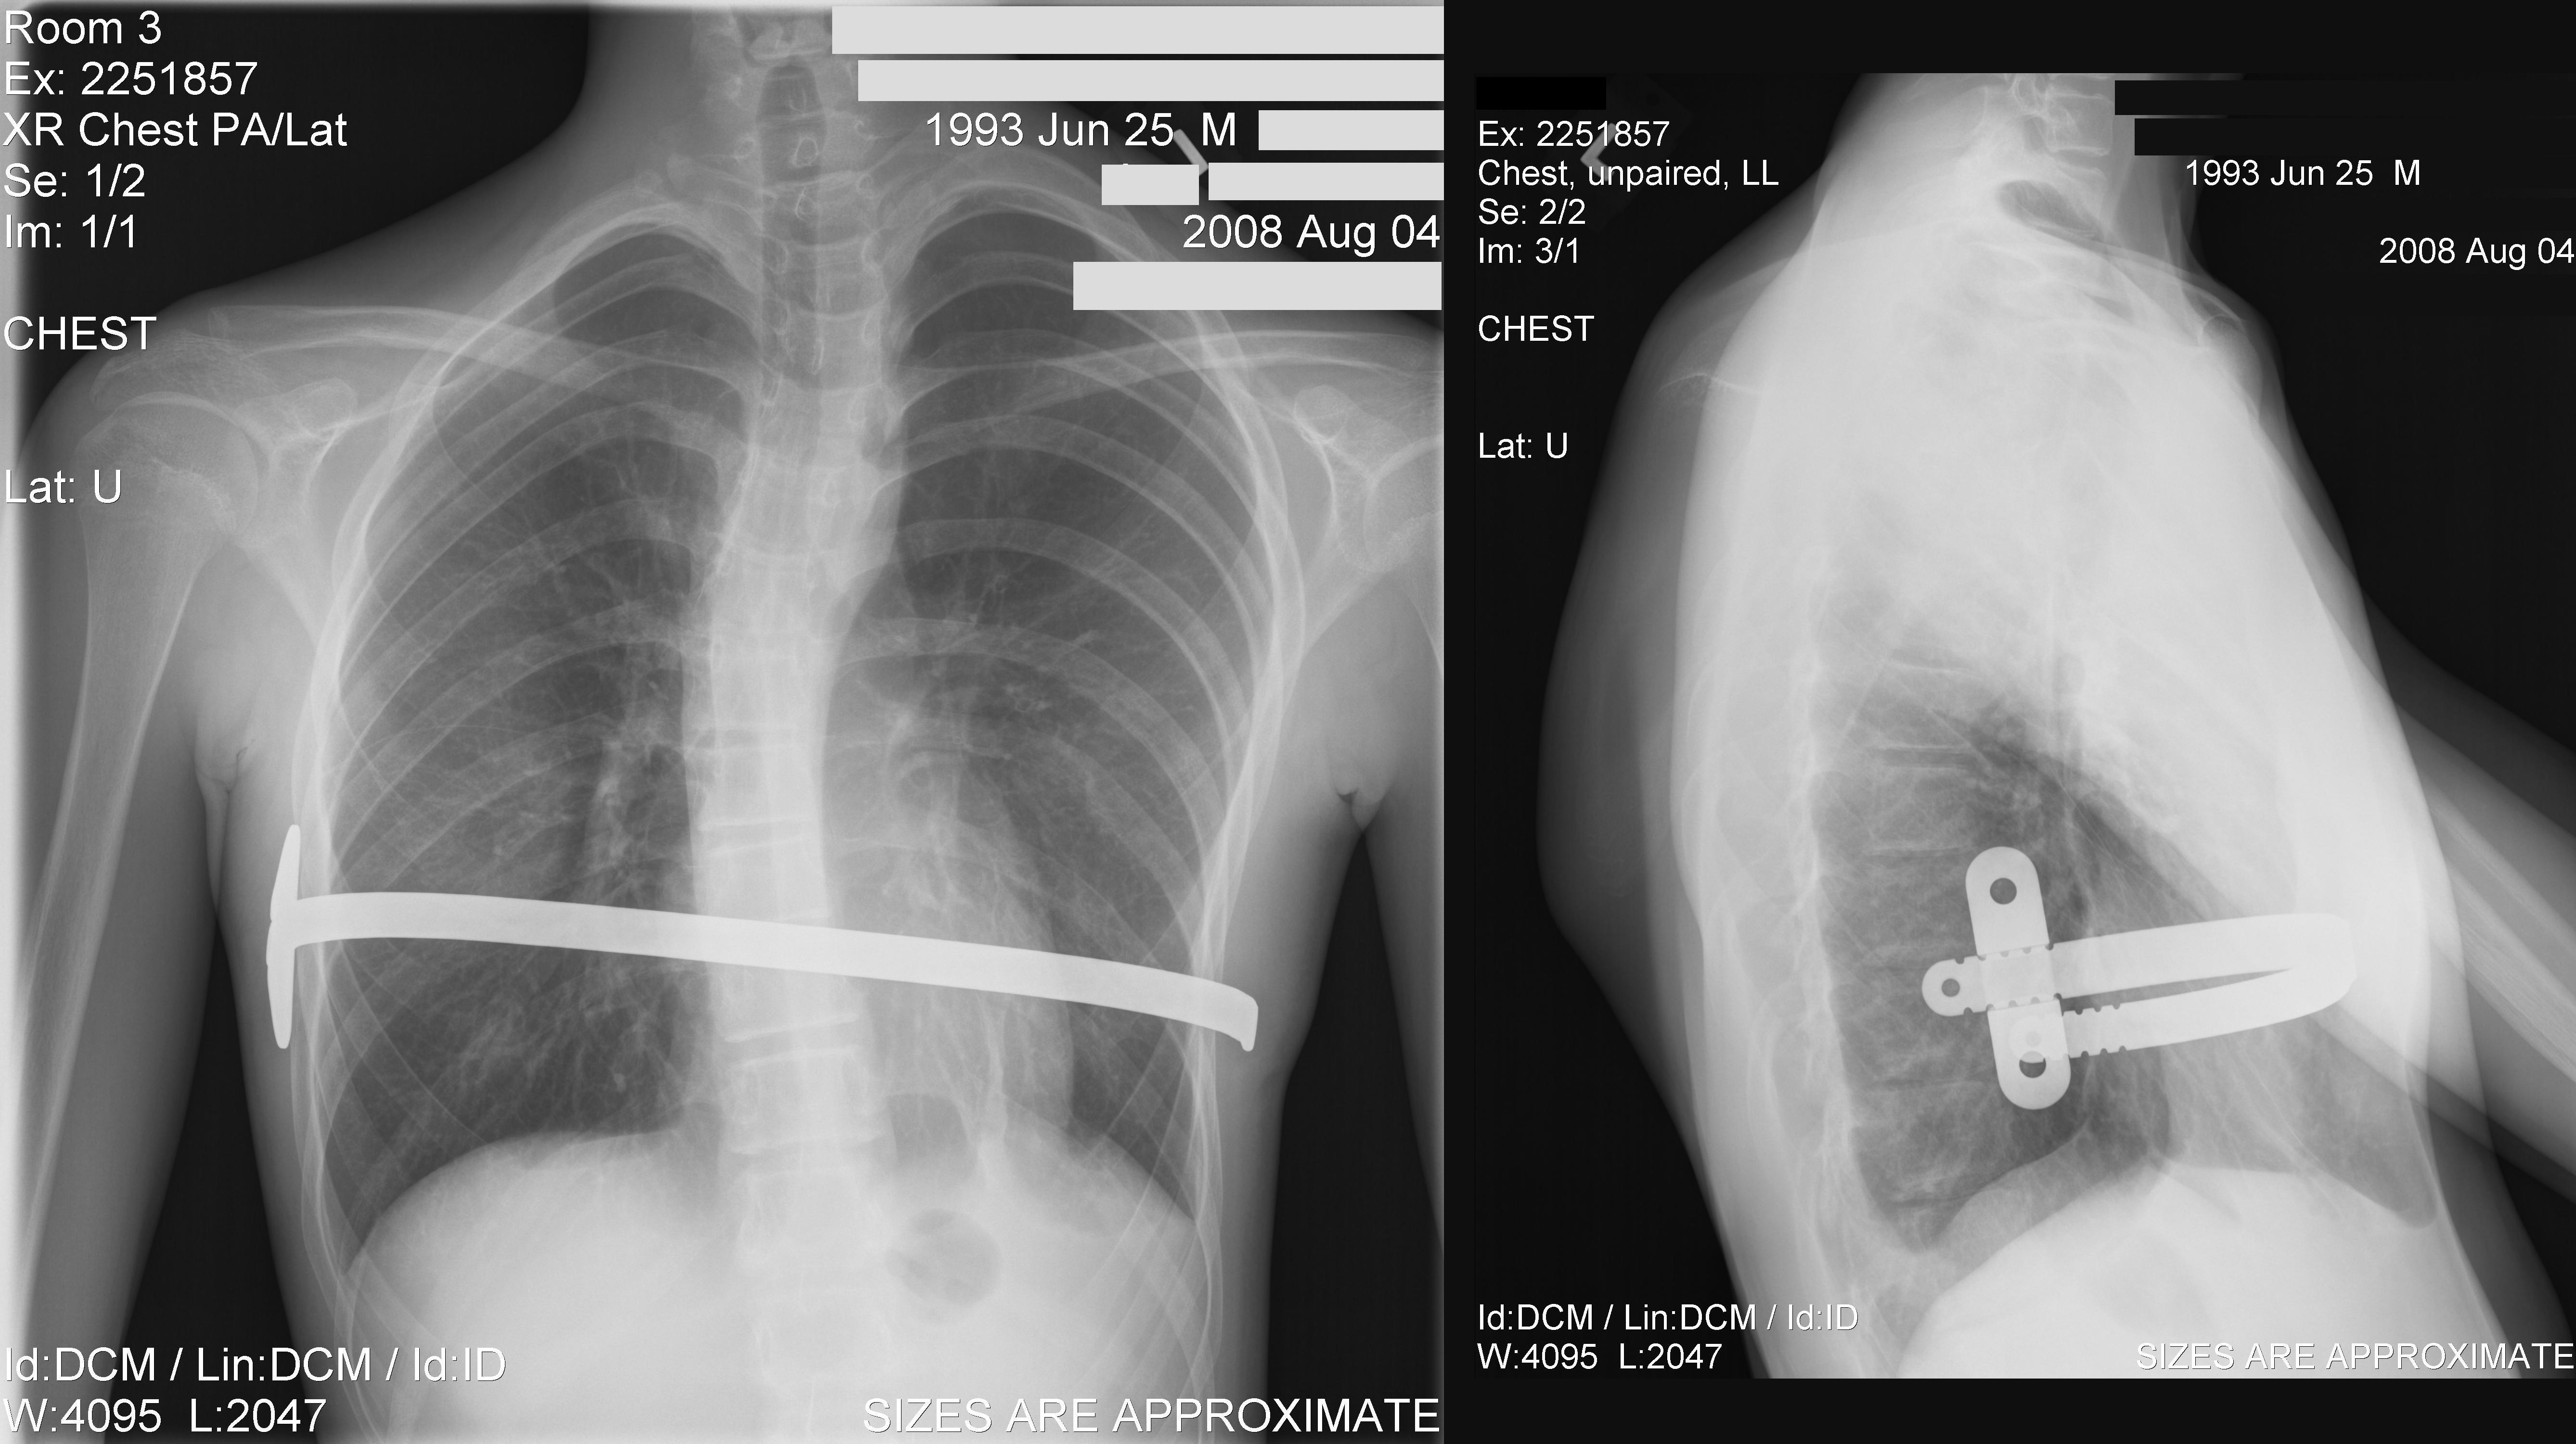

경미한 오목가슴은 교정이 필요하지 않다.[20] 심한 경우에는 침습적 시술이나 비침습적 시술, 또는 두 가지 모두를 사용하여 치료할 수 있다. 수술 전에는 일반적으로 CT 스캔, 폐 기능 검사, 심장학 검사(청진, ECG 등)를 포함한 여러 검사를 시행한다.[21] CT 스캔 후에는 Haller 지수를 측정하는데, 이는 횡경(늑골 내부 수평 거리)과 전후경(척추와 흉골 사이 최단 거리)의 비율이다.[22] Haller 지수가 3.25보다 크면 심각한 것으로 간주되며, 정상 가슴은 2.5이다.[17][23][24] 심폐 기능 검사는 폐활량과 심장 잡음을 확인하는 데 사용된다.[25]오목가슴 교정을 위한 최선의 수술 방법에 대해서는 논란이 있어 왔다. 외과 의사는 각 개인의 특성에 맞는 수술 방법을 선택해야 한다.[43] 수술적 교정은 호흡 문제나 심장 잡음 같은 기능적 증상을 개선하며, 극심한 경우 영구적 손상이 없다면 효과를 볼 수 있다.[44] 오목가슴 수술은 심혈관 기능을 유의미하게 개선하는 것으로 나타났지만,[45] 폐 기능 개선 여부는 아직 결론이 나지 않았다.[46] 오늘날 가장 인기 있는 오목가슴 수술 기술 중 하나는 MIRPE 또는 너스(Nuss) 수술로 알려진 최소 침습 수술이다.[47]

1987년, 버지니아주 노퍽의 어린이 왕의 딸 병원의 도널드 너스는 오목가슴의 최초 최소 침습적 교정술(MIRPE)을 시행했으며[52], 1997년 학회에서 발표했다.[52][53][54] "너스 시술"로 널리 알려진 이 2단계 시술은 하나 이상의 오목한 강철 막대를 흉부 내, 흉골 아래에 삽입하는 과정이다.[55] 막대는 흉골을 바깥쪽으로 밀어 변형을 교정하도록 볼록한 위치로 뒤집는다. 막대는 약 2년 동안 신체 내에 유지되지만, 최근에는 최대 5년까지 유지하는 경우도 있다. 뼈가 제자리에 굳어지면 외래 수술을 통해 막대를 제거한다. 처음에는 10세 미만 어린이를 대상으로 설계되었지만, 10대 후반과 20대 환자에게도 너스 시술이 성공적으로 이루어지고 있다.[56]

일본에서는 누두흉 수술의 표준적인 술식으로 너스(Nuss) 수술법이 자리 잡았다. 늑골 아래에 티타늄 또는 스테인리스 스틸 재질의 바와 필요에 따라 안정장치를 2~3년 동안 삽입한 후 제거하여 흉골을 들어 올리는 방법이다. 장점으로는 흉골 융기술 변법에 비해 가슴 앞부분의 흉터가 작고 눈에 띄지 않으며, 뼈를 절개하지 않으므로 흉골 융기술 변법과 같은 뼈에서 오는 통증이 없다. 또한, "함몰 치료" 외에 "[https://www.med.kagawa-u.ac.jp/~keisei/routo/basic/thinchest/ 편평 흉곽]"도 해결한다. 단점으로는 흉골 융기술 변법에서는 하지 않는 옆구리 부분 절개(바 삽입을 위해)로 수술 후 며칠 동안 상처 부위에 통증이 따르며, 경막외 마취가 필요하다. 또한, 합병증 위험도 있는데, 가와사키 의과대학 및 니시노미야 와타나베 심장 뇌·혈관 센터 누두흉 치료 센터 연구에서 스테로이드가 효과적이었다고 발표되었다. 수술 후 바 제거까지 바 편위를 방지하기 위해 유도와 같은 운동 제한이 있다.